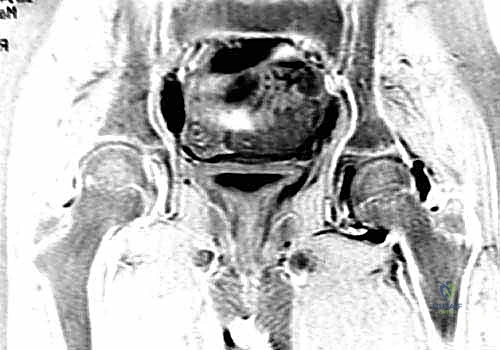

في الحالات المتقدمة من مرض بيرثيز، يتضخم رأس الفخذ المشوه ويبرز خارج التجويف الحُقي (Subluxation). وعندما يحاول الطفل إبعاد ساقه (Abduction)، يصطدم الجزء البارز من رأس الفخذ بحافة التجويف والشفا الحُقي، مما يؤدي إلى سحقهما وتدميرهما. هذه الظاهرة الخطيرة تُعرف باسم الانزلاق المفصلي المحوري (Hinge Abduction)، وهي السبب الرئيسي للألم وتدمير المفصل. هنا يأتي دور جراحة دعم الشفا لإنقاذ الموقف.

عندما يتضخم رأس الفخذ ويفقد شكله الكروي، فإنه ينزلق جزئياً خارج التجويف الحُقي. في هذه الجراحة، يقوم الأستاذ الدكتور محمد هطيف بأخذ طُعم عظمي (Bone Graft) - غالباً من عظم الحوض نفسه - وتثبيته فوق الحافة الخارجية للتجويف الحُقي. هذا الطُعم العظمي يخلق "سقفاً" إضافياً أو "رفرفاً" يغطي الجزء البارز من رأس الفخذ.

5. بناء الرفرف (Creating the Shelf)

هنا تتجلى مهارة الأستاذ الدكتور محمد هطيف؛ حيث يقوم بإحداث شق دقيق فوق حافة التجويف الحُقي، ويدرج الطُعم العظمي بقوة داخل هذا الشق. يتم توجيه الطُعم بحيث يمتد للخارج وللأسفل، مشكلاً سقفاً صلباً يغطي رأس الفخذ البارز.